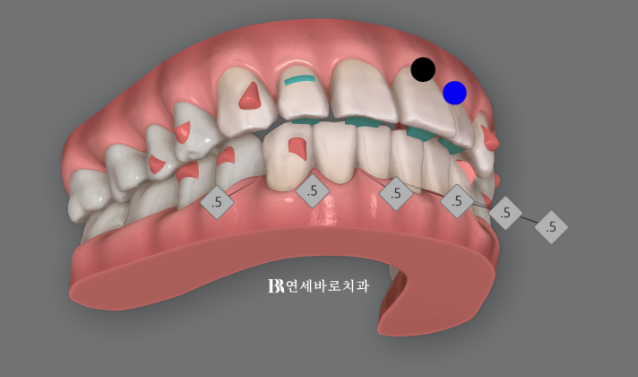

인비절라인 치료 중에는 치아에 어태치먼트가 필요합니다.

인비절라인으로 교정이 잘 안 되던 과거와 현재가 명확히 나뉘는 기준이 바로 이 어태치먼트의 유무입니다.

50대 치아벌어짐 적절한 치료계획과 적당한 갯수의 올바른 어태치먼트의 배치

각 치아마다 다른 전략을 세워 치료를 하면 가장 빠르고 좋은 결과를 만듭니다.